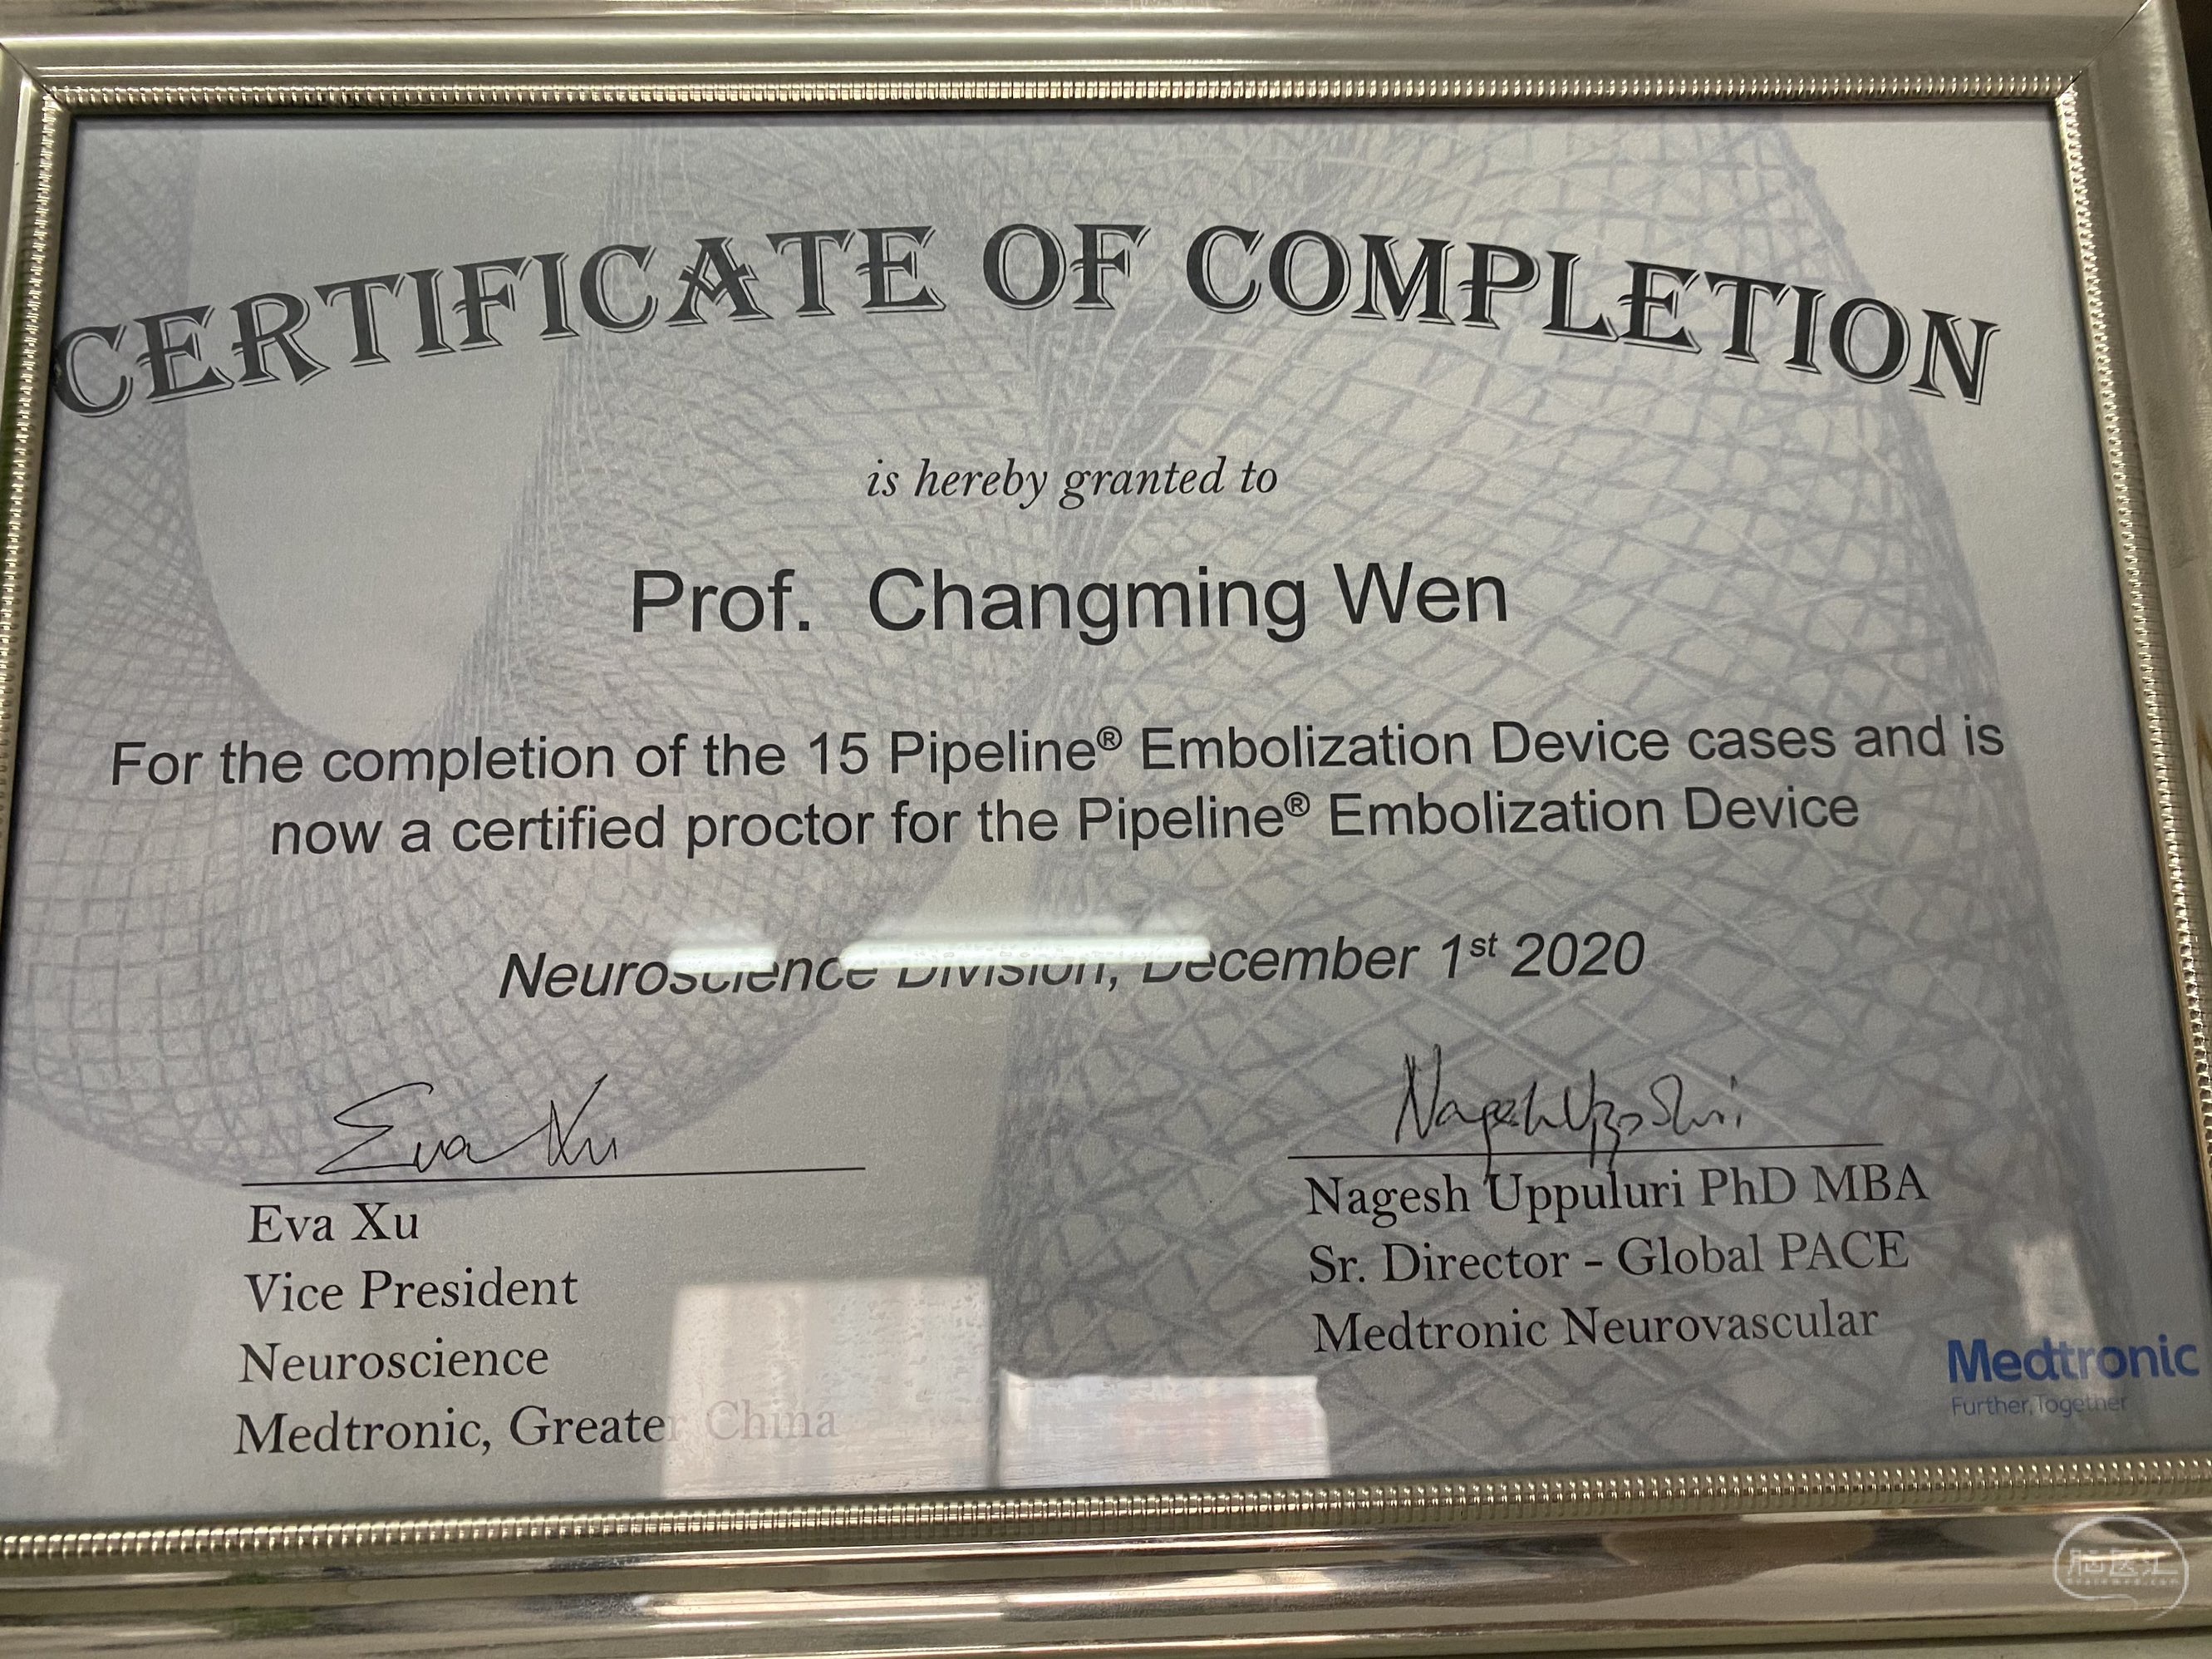

今日手术,TJG,M62Y,一期左侧颈动脉狭窄支架植入,二期椎动脉V4段多发夹层动脉瘤伴狭窄,常规支架辅助栓塞方法复杂又危险,血流导向装置植入快捷又安全。南阳市中心医院神经内科脑血管病介入团队pipeline flexFD植入两人导师资格。

今日手术,TJG,M62Y,一期左侧颈动脉狭窄支架植入,二期椎动脉V4段多发夹层动脉瘤伴狭窄,常规支架辅助栓塞方法复杂又危险,血流导向装置植入快捷又安全。南阳市中心医院神经内科脑血管病介入团队pipeline flexFD植入两人导师资格。